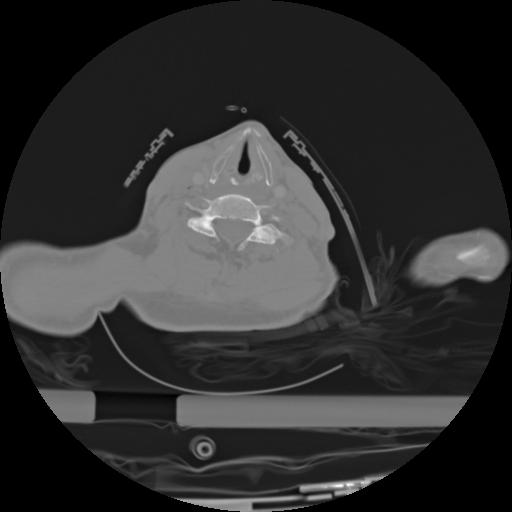

21 ANGIO,CE,Axial,3.0,ANGIO,,